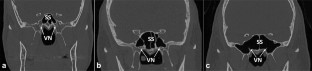

In total, 320 maxillofacial CT-scans were retrospectively assessed. Subjects equally divided among males and females (age range 18–94 years) were divided into three groups according to the profile of Vidian nerve protrusion: type 1: Vidian nerve inside the sphenoid corpus; type 2: partially protruding into the sphenoid sinus; and type 3: entirely protruding into the sphenoid sinus through a stalk. Volume of sphenoid sinuses was extracted through the ITK-SNAP-free software and automatically calculated. Possible statistically significant differences in prevalence of the three types between males and females were assessed through Chi-squared test (p < 0.05). Differences in volume of sphenoid sinuses in subjects included within the three types were assessed through one-way ANOVA test (p < 0.05), separately for males and females.

Fig. 1